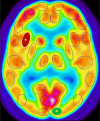

Methods: Fluorodeoxyglucose-18 positron emission tomography measured brain metabolism in regions of interest, and RNA analysis of blood samples assessed gene expression pre- and post-sleep deprivation. Mixed model regression and principal component analysis identified significant genes and regional metabolic changes.

Results: There were 23 and 28 differentially expressed probe sets for the main effects of sex and sleep deprivation, respectively, and 55 probe sets for their interaction (FDR-corrected p < 0.05). Functional analysis of genes affected by sleep deprivation revealed pathway enrichment in nucleoplasm- and UBL conjugation-related genes. Genes with significant sex effects mapped to chromosomes Y and 19 (Benjamini-Hochberg FDR p < 0.05), with 11 genes (4%) and 29 genes (10.5%) involved, respectively. Differential gene expression highlighted sex-based differences in innate and adaptive immunity. For brain metabolism, sleep deprivation resulted in significant decreases in the left insula, left medial prefrontal cortex (BA32), left somatosensory cortex (BA1/2), and left motor premotor cortex (BA6) and increases in the right inferior longitudinal fasciculus, right primary visual cortex (BA17), right amygdala, left cerebellum, and bilateral pons.